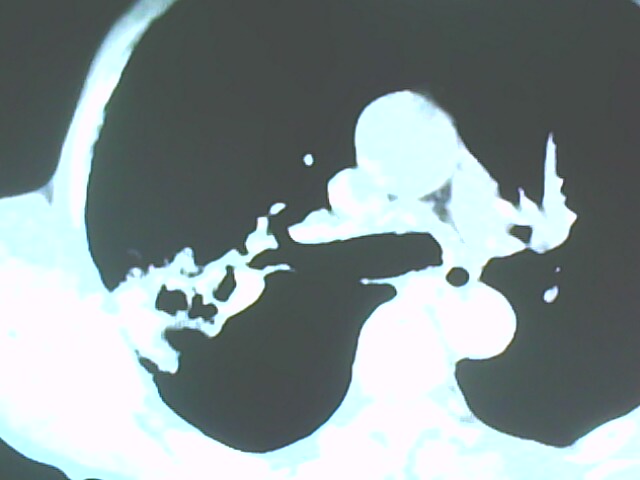

患者,男,66岁,以咳嗽、咳痰伴胸痛来就诊。

胸片提示右上肺占位病变。请各位老师看看ct。

从年龄及影像特征均支持癌性空洞。

右上肺后段肺癌:

典型癌性空洞(偏心性,壁厚薄不均,内壁不光整),周围毛刺较僵硬,且有刺突征和血管聚集征